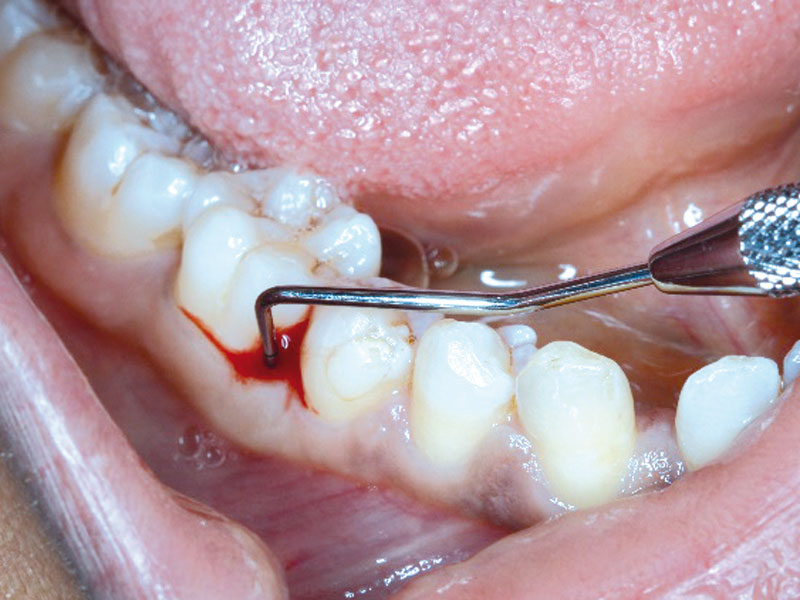

01/08 - PPD of 9mm at mesial of LR6Regeneration at LR6 with cerabone® and collprotect® membrane using simple papilla preservation technique - Dr. D. Chatzopoulou